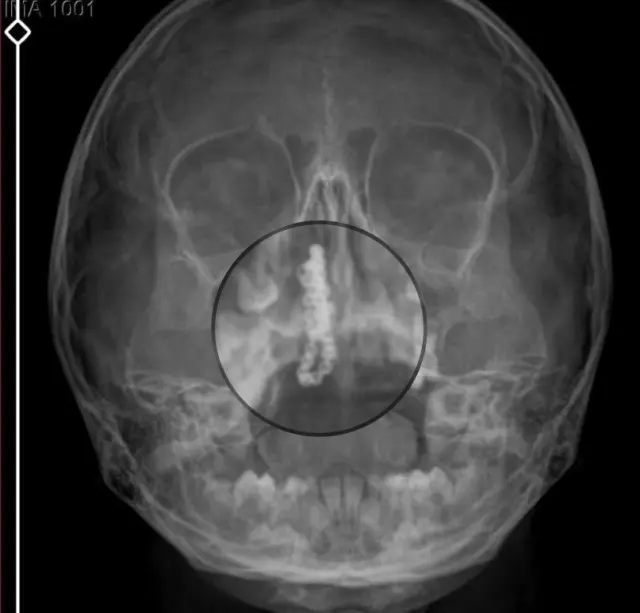

Devlet hastanesindeki doktorun incelemesi ve kapsamlı röntgen çekilmesi sonrası Polen’in burnunda metal cisim olduğu fark edildi. 2 yıldır burunda kaldığı değerlendirilip, küçük top şeklinde tırnak makası zinciri olduğu belirlenen cisim, başarılı ameliyatla çıkarıldı. Bir süre tedavisi sürdürülen Polen, sağlığına kavuşunca taburcu edildi. Özel hastane yetkilileri, konuyla ilgili açıklama yapmazken; aile suç duyurusunda bulunacaklarını söyledi.

Kızının burnundan sürekli siyah renkte akıntı olduğunu anlatan Gökhan Tekin, “Çocuğumun burnundan kanama ile sürekli siyah akıntı geliyordu. Özel hastaneye götürdüm. Özel hastanede film çekildi, hiçbir bulguya rastlanılmadığı söylendi. O siyah leke de enfeksiyona dayalı olan bir şey olduğu bize söylendi. Eve geldik, akıntı sürmesi üzerine bu kez devlet hastanesine başvurduk. Burunda metal zinciri fark ettiler. Böyle bir ihmalkarlık olabilir mi? Özel hastaneye gidiyoruz, paramızla rezil oluyoruz. Zincir, 2 yıldır burnunda ve devletimizin hastanesinde iyi bir doktorumuz zinciri ortaya çıkarıyor, kızım ölümden dönüyor. Ben sonuna kadar bu işin peşini bırakmayacağım. Sonuna kadar hukuk mücadelesi vereceğim. Bu da diğer hastalarımıza ibret olsun. İşte, bakın koca bir zincir. ‘Bulguya rastlanılmadı’ deniliyor” dedi.

Kızının ameliyat sonrası durumunun iyi olduğunu söyleyen Tekin, “İnanır mısınız bize ‘Evde soba mı yanıyor? Acaba kömür isten dolayı mıdır bu?’ dendi. Böyle bir şey olabilir mi? Ameliyattan çıkan parmağım kadar zincir. Devlet hastanesindeki doktor da ‘Bu nasıl gözden kaçılabilir? Böyle bir pozisyon nasıl görülmeyebilir?’ yorumunda bulundu. Allah’a şükür olsun atlattık. Şu anda durumu, vaziyeti iyidir. Ben şuna inanıyorum doktor da bir şans işidir. Bakın paramızla özele gideriz ya hani bizde, daha iyi ilgilenirler. Oysa devlet hastanesindeki doktorumuz olayı meydana çıkardı” diye konuştu.